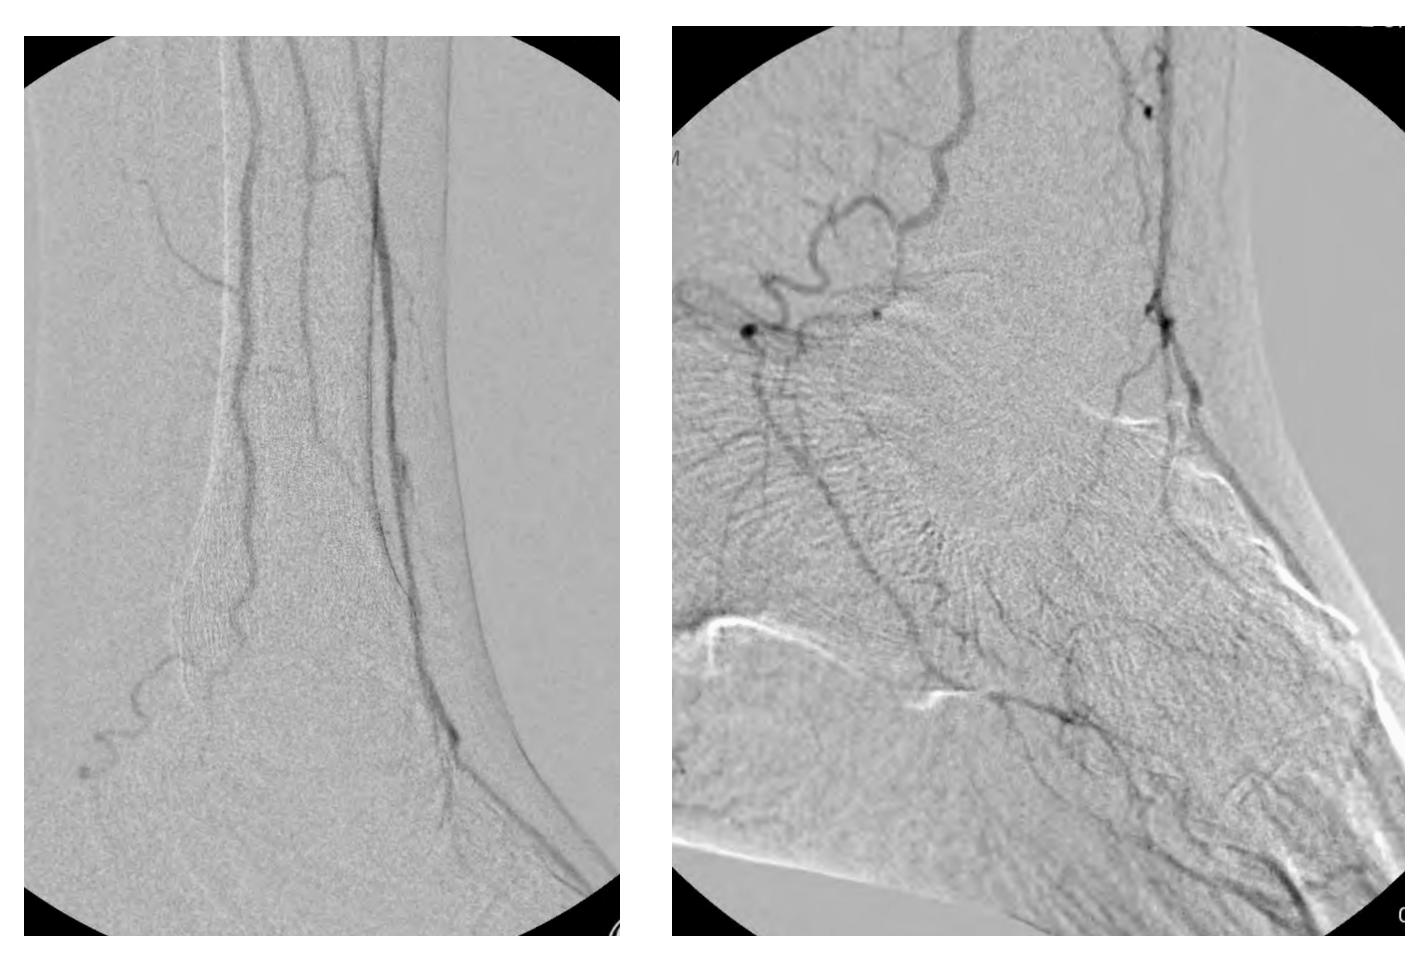

After being medically optimized, the patient was scheduled for an angiogram. The angiogram revealed occlusion of the anterior and posterior tibial arteries with reconstitution of the plantar arteries via the peroneal artery as well as reconstitution of the dorsalis pedis artery via the peroneal artery (Figures 2, 3, and 4).

The anterior tibial artery was chosen as the target of revascularization given the predominant supply to the forefoot via the dorsalis pedis artery compared with the lesser supply via the diminutive plantar arteries. An “up and over” approach from a contralateral right common femoral artery access was successful in crossing to the distal segment of the anterior tibial artery in antegrade fashion; however, further crossing could not be achieved in antegrade fashion (Figure 5).

In order to cross and treat the remainder of the distal anterior tibial artery occlusion, a retrograde pedal access was desired. Due to concerns about puncture-related injury to the dorsalis pedis artery that could potentially compromise the patient’s existing flow as well as a potential surgical bypass target, retrograde pedal access of the patent dorsalis pedis artery was avoided at this point. Instead, a plan was made to obtain retrograde pedal access of the occluded segment of the distal anterior tibial artery above the reconstitution point (Figure 6).